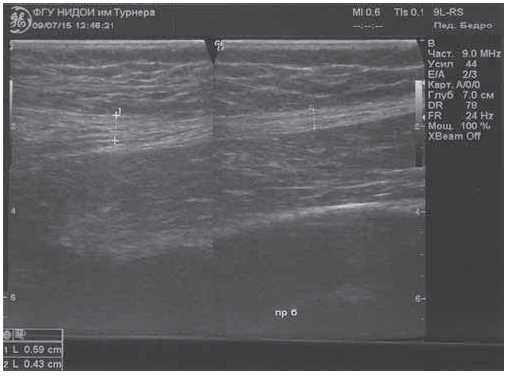

Ultrasound examination (US) of the hip joints were performed using GE LoGIQ-7 apparatus and showed a hyperechoic cord with a thickness in the upper third of the thigh of 5.9 mm, and in the middle third of the thigh of 4.3 mm, located along the lateral surface of the right thigh in the structure of the muscular tissue (Fig. 3).

Fig. 3. Fibrous cord in the soft tissues of the right thigh